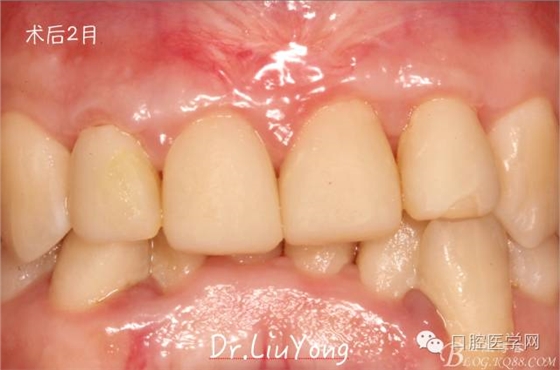

術(shù)后兩周,復(fù)查,A1達(dá)到了完全的根面覆蓋,B1牙齦退縮由原來的3.5mm減少到1mm,B2近中牙齦也得到部分的恢復(fù),同時所有牙齦邊緣都通過手術(shù)增厚。如上圖

膜齦手術(shù)后2月復(fù)查,可以明顯觀察到,B12之間的牙齦乳頭明顯高度增加,黑三角得到很大改善,如下圖: